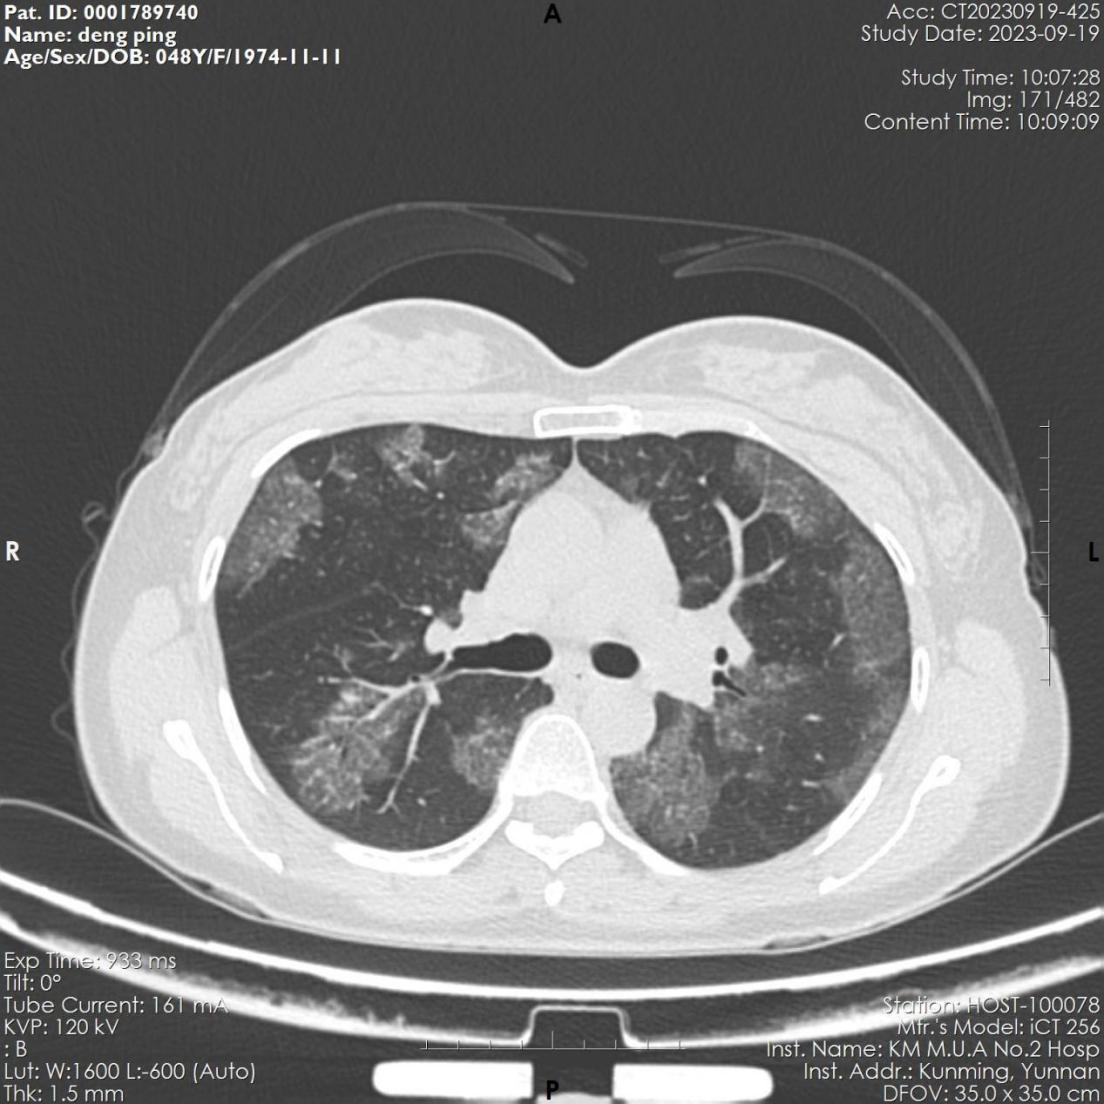

该患者,女,48岁,近3月来反复出现活动后胸闷气促。6月份因感染肺炎住院治疗,经抗病毒治疗后,咳嗽、咽痛等呼吸道症状缓解。9月因胸闷气促再发加重,来到华人色情 全科医学科就诊,复查胸部CT显示肺部病变未见吸收,病变呈弥漫磨玻璃影,病变与正常组织分界较清,呈“地图征”,考虑“间质性肺疾病-肺泡蛋白沉积症可能”收住全科医学科。入院后完善电子支气管镜检查示双侧支气管未见明显异常,但各管腔内的肺泡灌洗液呈乳白色,肺泡灌洗液细胞学病理检查示肺泡巨噬细胞中间粉红色颗粒样物质,D-PAS和PAS染色阳性。结合病史、胸部CT、肺泡灌洗液呈乳白色、PAS染色阳性,该患者确诊罕见病“肺泡蛋白沉积症”。